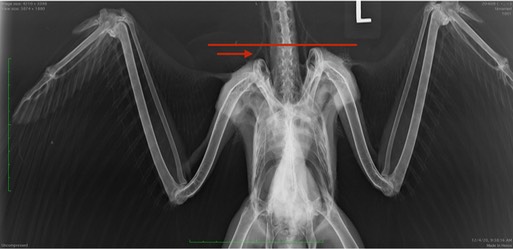

A very unlucky Red-tailed Hawk was found in a field near La Grande, OR. ODFW transported the hawk to Pendleton. An exam revealed the hawk was emaciated, had wounds on the right wing and left foot consistent with electrocution and abnormalities in the right shoulder. A radiograph showed the right shoulder was significantly lower than the left shoulder. The hawk must have collided with something resulting in an injury making it impossible for her to fly.

Although it is hard to know for certain, the shoulder injury appears to be much older than the electrocution injuries. Perhaps the hawk injured her shoulder, spent several weeks on the ground, healed up sufficiently to begin flying, managing to get up to the top of a power pole, only to be electrocuted. That would indeed be unlucky.

The shoulder injury may prevent the hawk from flying well enough to be released. Of additional concern is her left leg and foot. If you look closely at the photo below you will notice the left foot is slightly swollen and there is a color difference between the feet. The electrical shock from touching two wires has compromised the circulation. The hawk still has full use of the foot so there is hope that the damage is not permanent. Time will tell. For now, she has an excellent appetite which is always a good sign. She is about to swallow that mouse in one gulp. We are slowly increasing the amount of food she gets each day so as not to overwhelm her gut in her emaciated state.